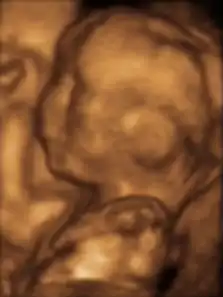

Ultrasonido 3d

El Ultrasonido de 3d es una técnica de ultrasonido, usada frecuentemente durante el embarazo, que provee imágenes tridimensionales del feto.

Hay distintos modos de escaneo en ultrasonido médico y obstétrico. El modo de diagnóstico estándar es el escaneo en 2D.[1] En el escaneo fetal 3D en vez emitirse ondas de ultrasonido en línea recta, estas se envían en distintos ángulos. Los ecos que rebotan son procesados por un sofisticado programa de computadora, resultando en una imagen reconstruida del volumen de la superficie del feto o sus órganos internos, muy parecida a la manera en que la máquina de Tomografía axial computarizada construye una imagen con múltiples tomas de rayos X. Los ultrasonidos 3D permiten ver el ancho, el alto y la profundidad de las imágenes de la misma manera que una Película 3-D, pero no se muestra movimiento.

Los ultrasonidos 3D es mejor realizarlos entre las semanas 24 y 32, e idealmente entre las semanas 26 y 30. Algunos centros aconsejan a sus clientes ir entre las semanas 26 y 28 para obtener las mejores imágenes.

Después de las 32 semanas hay una alta probabilidad de que el feto haya bajado en la pelvis y sea casi imposible obtener imágenes 3D. Asimismo como el bebé es más grande hay menos espacio y es más difícil conseguir una buena imagen.